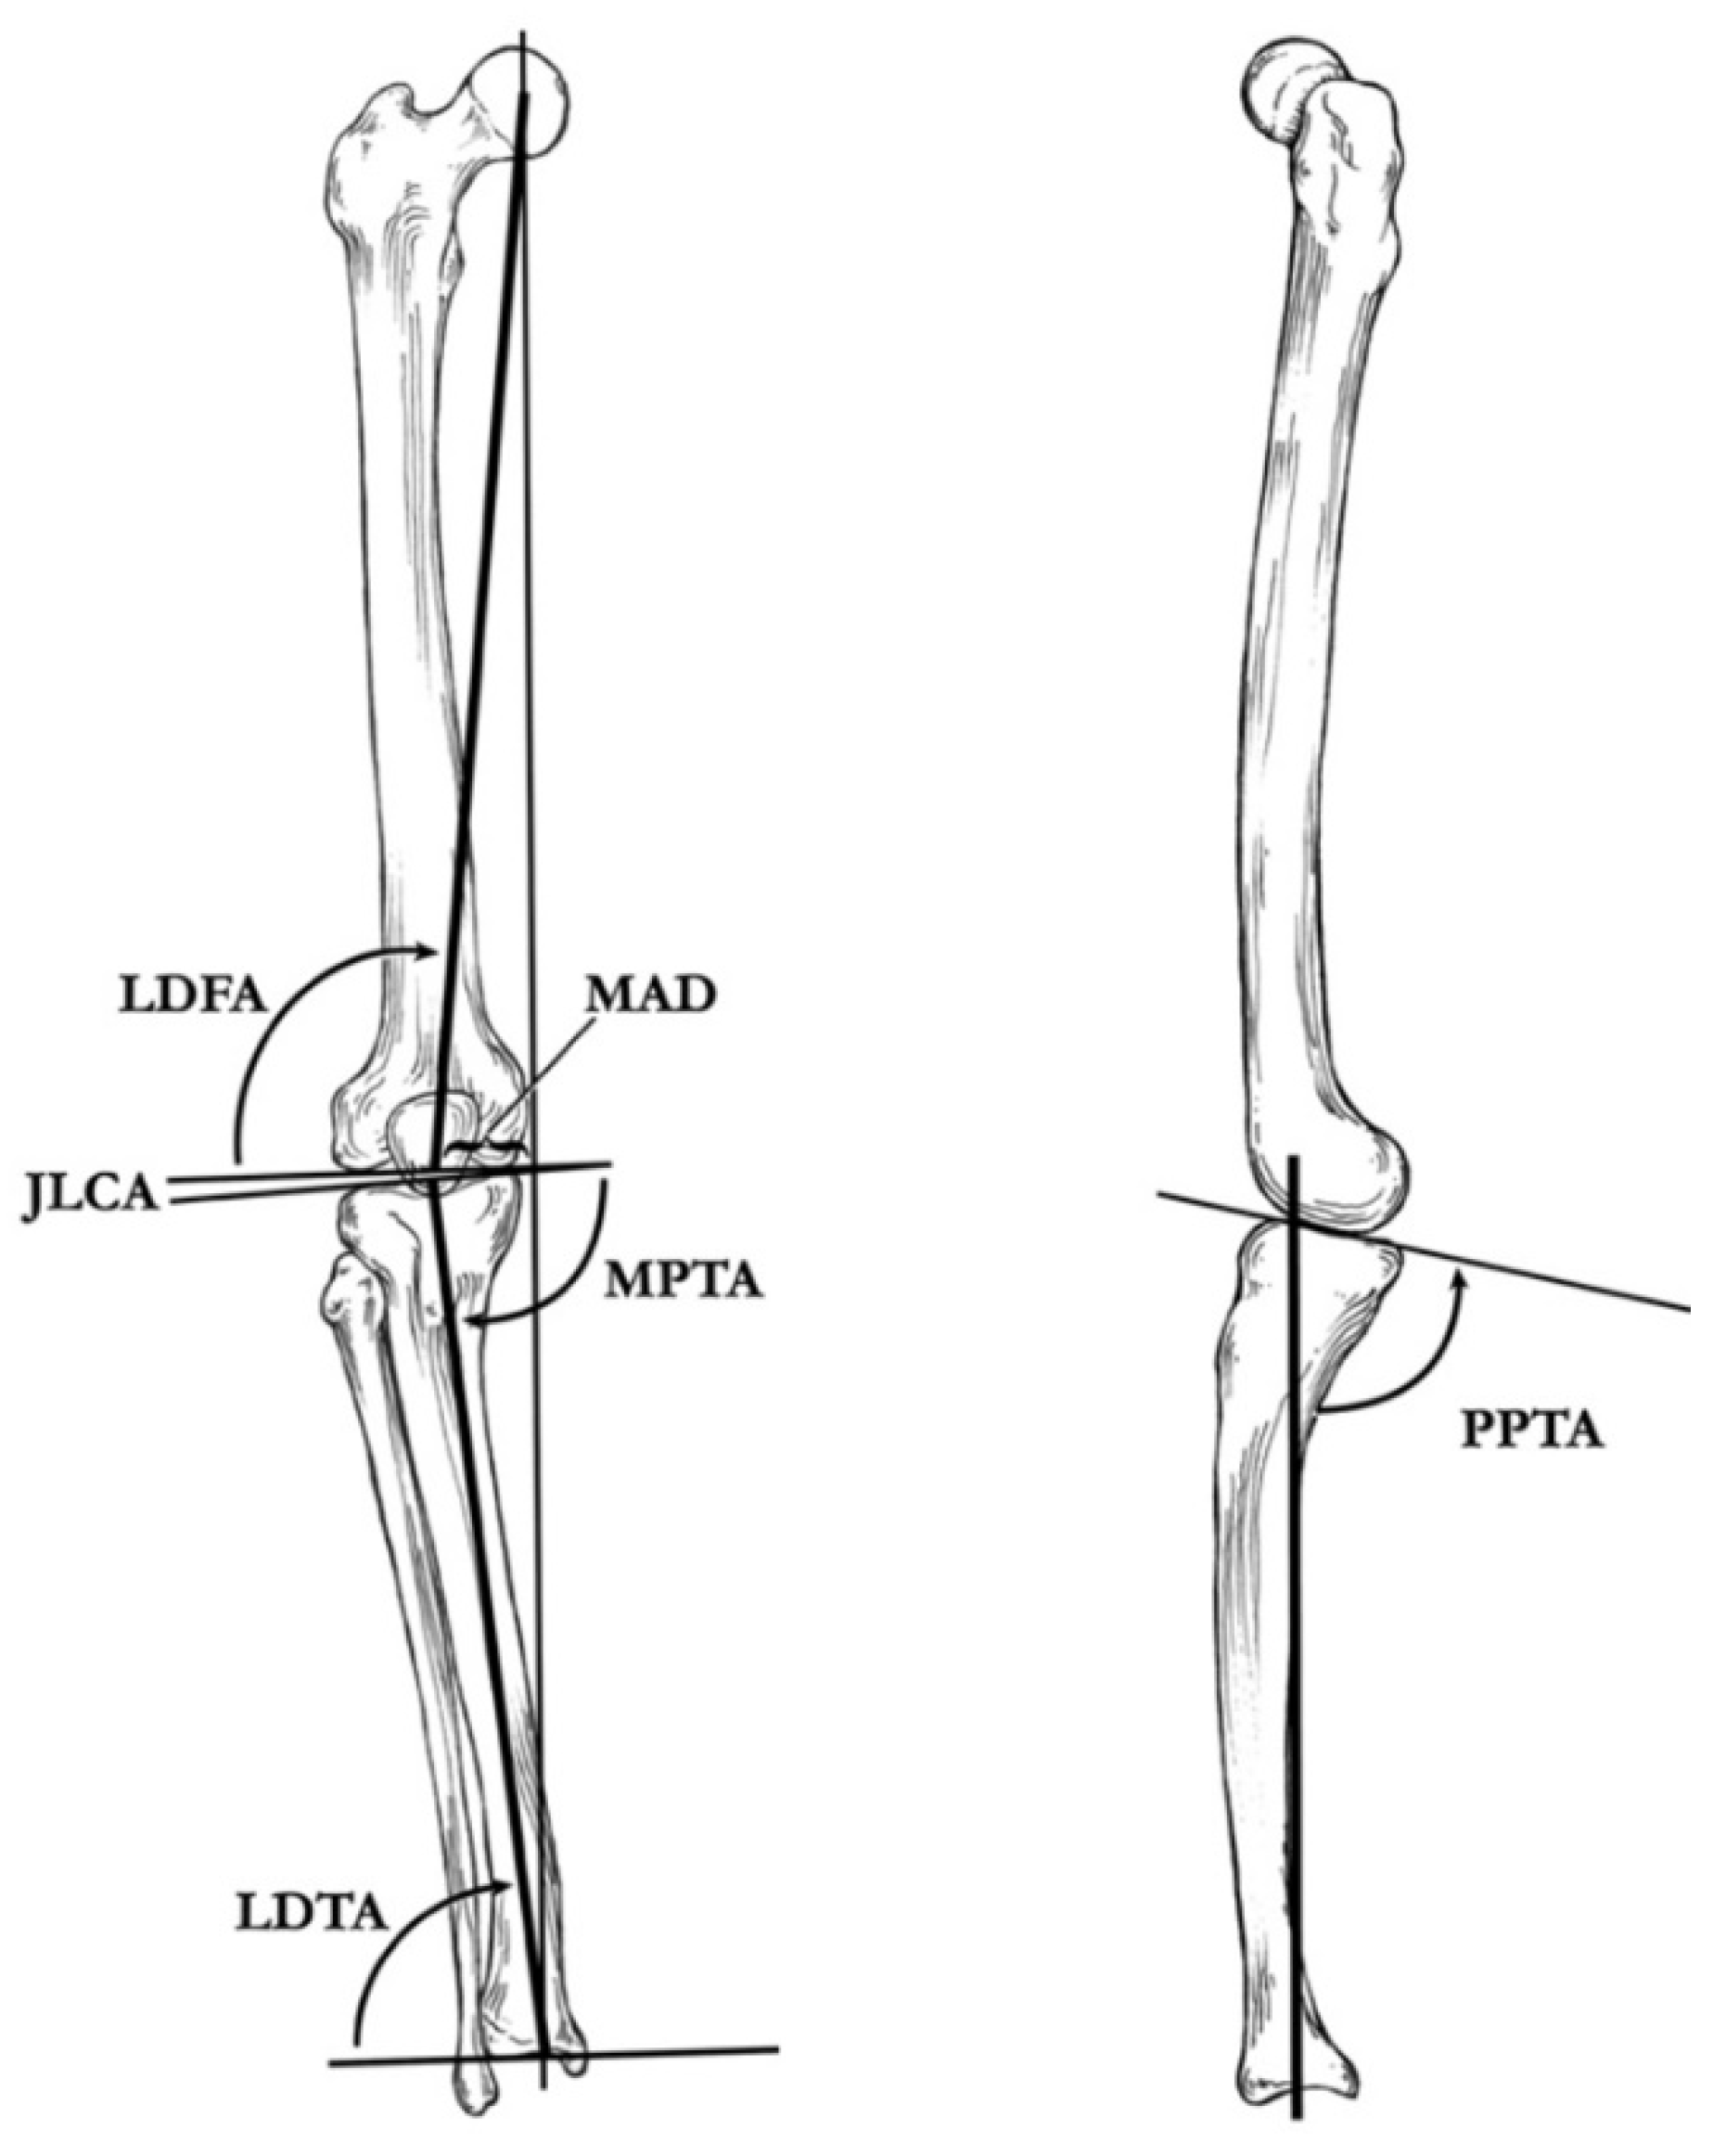

5. Radiographic Analysis

10. Surgical Planning